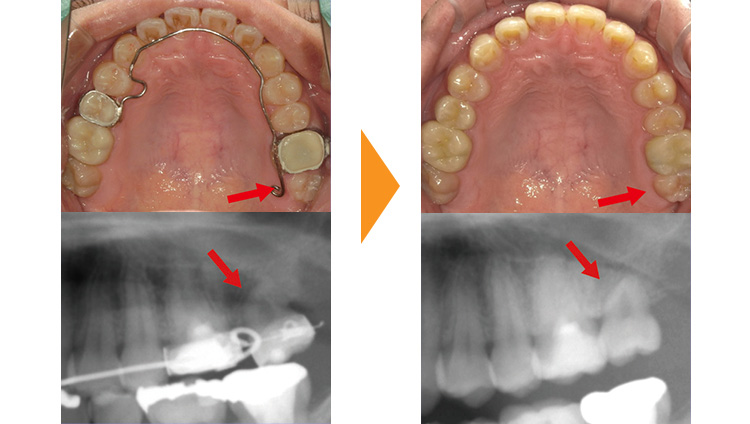

紹介元の歯医者さんで奥歯を抜歯しないといけないと言われた患者様です。予後不良の左上7を抜歯後、部分矯正にて左上8の牽引・排列を行った例となります。

リンガルアーチとワイヤーを使用し、約9か月で排列しました。

矯正後、仮歯の修正をしていただき治療は終了となります。(赤矢印)

この方のように全体的な歯並びに問題はないものの、むし歯が原因で抜歯になってしまった場合に部分的な矯正治療が効果的な場合があります。

矯正治療にて本来であれば使えなかった親知らずを使用し、インプラントや入れ歯を回避することができました。